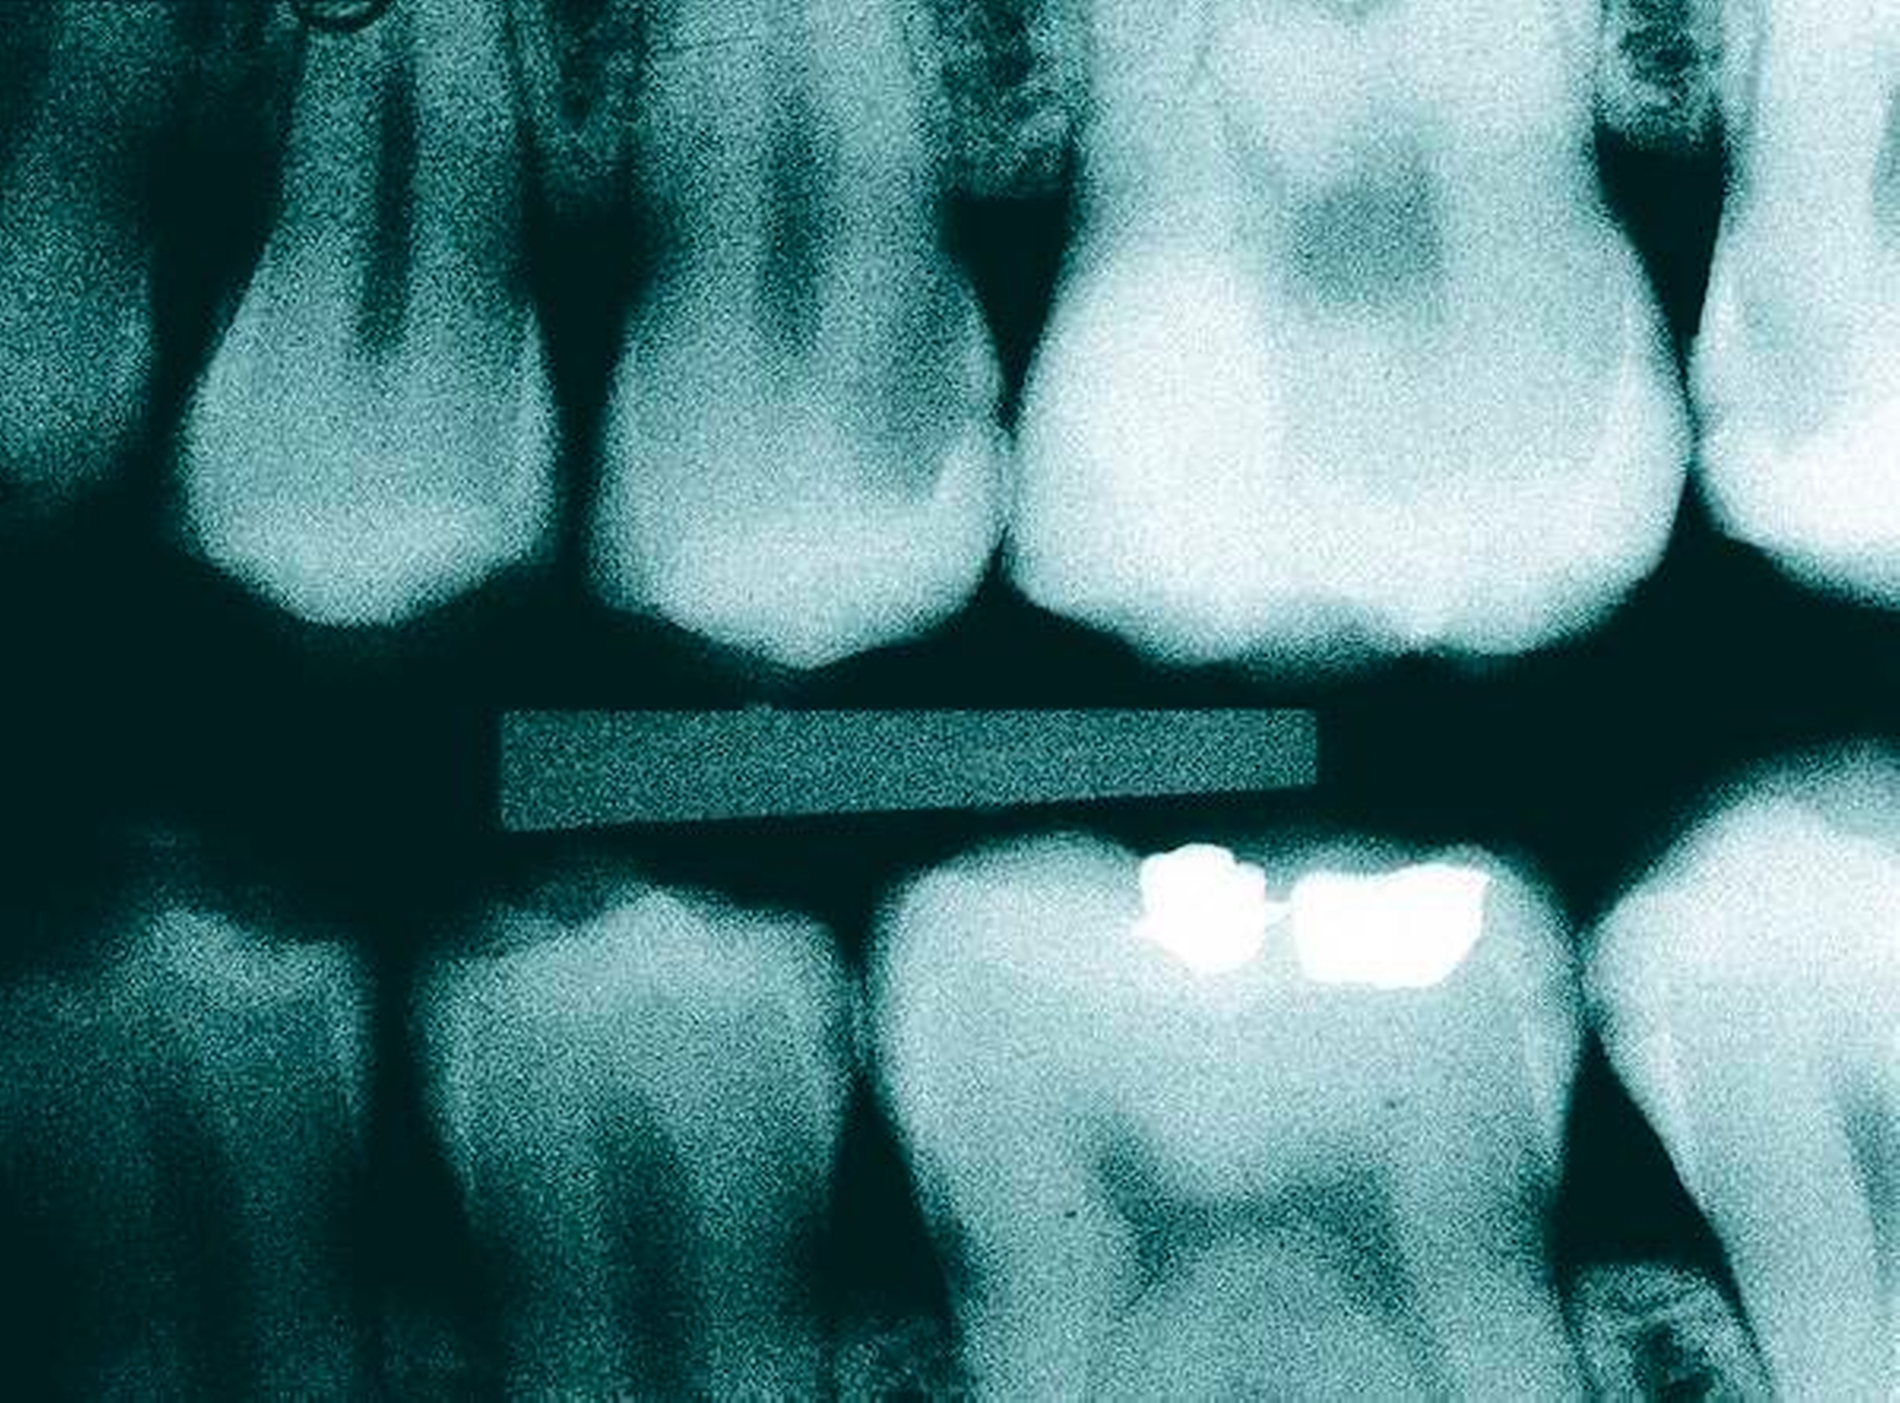

Nachgewiesenermaßen können Calciumsilikat-Zemente die Pulpa zur Bildung von Hartgewebe (Tertiärdentin) stimulieren und sind daher für die Versorgung tiefer kariöser Defekte nach Exkavation und somit für die Vitalerhaltung der Pulpa sehr gut geeignet [15, 21]. Nach indirekter Überkappung mit Biodentine kommt es reproduzierbar zur Ausheilung einer reversiblen Pulpitis [45]. Auch wenn mehr klinische Langzeitstudien zur Vitalerhaltung der Pulpa mit Calciumsilikat-Zementen wünschenswert sind, scheinen nach bisheriger Datenlage Calciumsilikat-Zemente für die indirekte Überkappung der Pulpa besser geeignet zu sein als Calciumhydroxid [2]. Für die direkte Überkappung wurde nachgewiesen, dass Calciumsilikat-Zemente zu besseren klinischen Ergebnissen und höheren Erfolgsraten führt als Calciumhydroxid [50, 60, 63]. Hinsichtlich der Hartgewebebildung ist es dabei unerheblich, ob man ein MTA-Zement oder Biodentine verwendet. Beide Arten von Calciumsilikat-Zement führen beim Menschen zu einer identischen Hartgewebsbrückenbildung [68] (Abbildungen 3 bis 10).